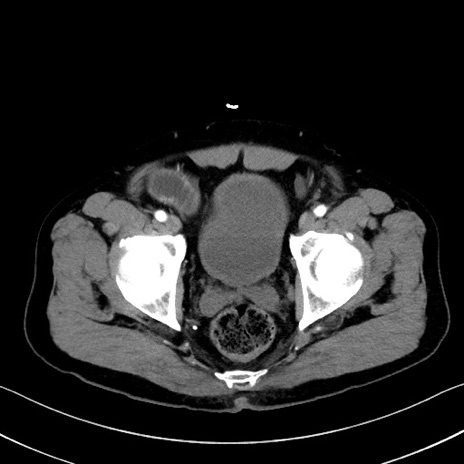

冠状断像

【症例】70歳代 男性

【主訴】腹部膨満、嘔吐

【現病歴】昨日より腹部膨満感出現。本日増悪し、仙痛出現。嘔吐あり、受診。

【既往歴】糖尿病、胆摘後

【身体所見】BP 149/80mmHg、HR 74/min、BT 35.9℃、腹部:膨満、軟、圧痛なし。腸雑音減弱あり。上腹部正中切開瘢痕あり。

【データ】WBC 13500、CRP 1.72